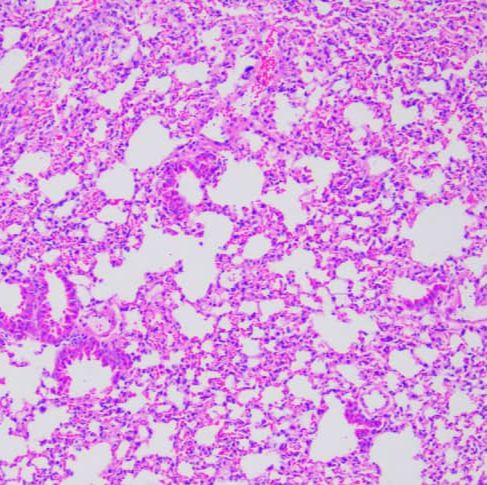

HE染色

简称HE染色法 ,石蜡切片技术里常用的染色法之一 。染液为碱性 ,主要使细胞核内的染色质与胞质内的核糖体着紫蓝色 ;伊红为酸性染料 ,主要使细胞质和细胞外基质中的成分着红色 。HE染色法是组织学、胚胎学、病理学教学与科研中最基本、使用最广泛的技术方法。

结果判读:细胞核被染成深蓝黑色;细胞浆被染成粉红色;软骨及钙盐被染成蓝色;胶原纤维染成淡粉红色,嗜酸性细胞及嗜酸性颗粒呈鲜红色;弹力纤维呈淡粉红色;某些蛋白性物呈粉红色等。